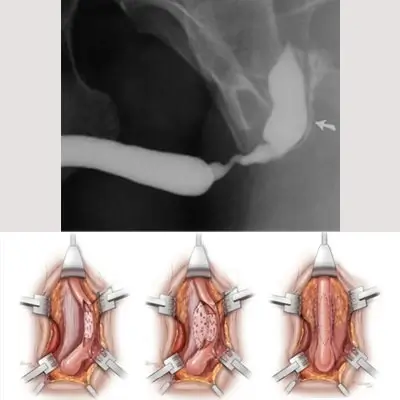

A urethral stricture occurs when scarring narrows the tube that carries urine out of your body. Urethral stricture restricts the flow of urine from the bladder and can cause a variety of medical problems in the urinary tract, including inflammation or infection. Urethroplasty involves surgically removing the narrowed section of your urethra or enlarging it. The procedure to cure urethral stricture may also involve reconstruction of the surrounding tissues. Tissues from other areas of the body, such as your skin or mouth (buccal mucosa ), may be used as a graft during reconstruction.

There are various types of urethroplasty procedures for urethral stricture.

• Bulbar Anastomotic

• Anastomitoc Urethroplasty – Membranous urethra

• Augmented Urethroplasty (Barbagli)

• Ventral Onlay

• Augmented Anastomosis

• Substitution Urethroplasty

If done beautifully, a well-done urethroplasty of urethral stricture can save you years in medical costs and procedures.